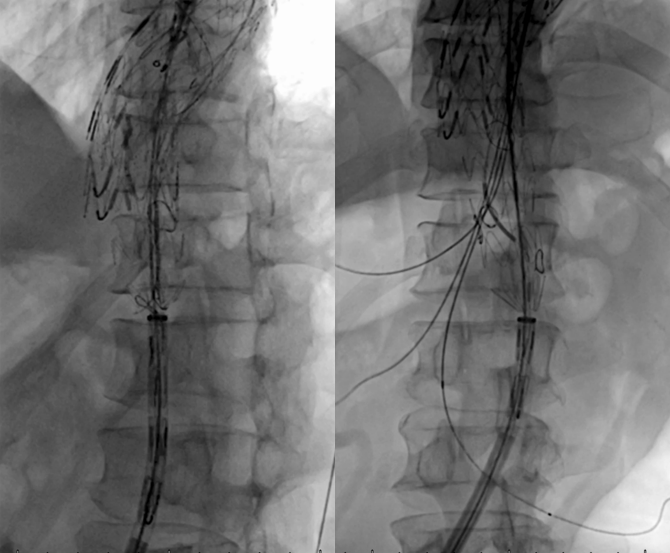

胸主支架,3D打印模型辅助精准开窗,缝短分支预防窗口漏

束径让支架可以上下移动和适度旋转,且不影响内脏血供

窗口依次打开,依次超选留置导丝

依次经预开窗口超选腹腔干、肠系膜上、左肾、右肾动脉

释放束径导丝

逐一植入桥接支架